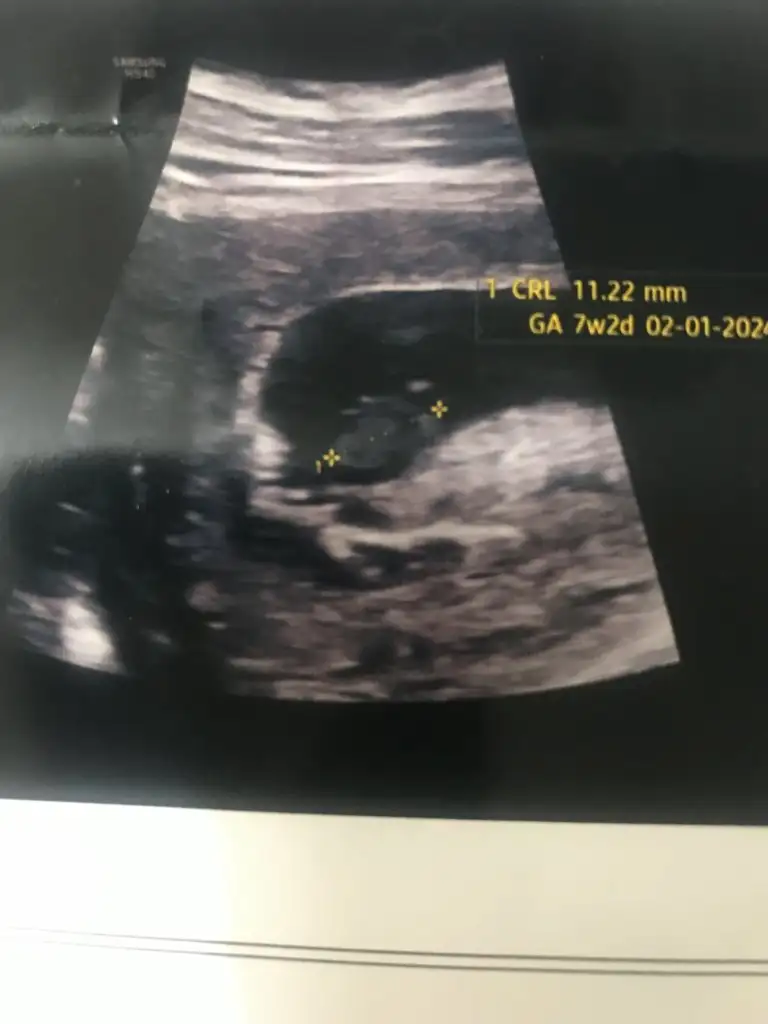

Bebek şükür iyi.

9+4 olmuş.